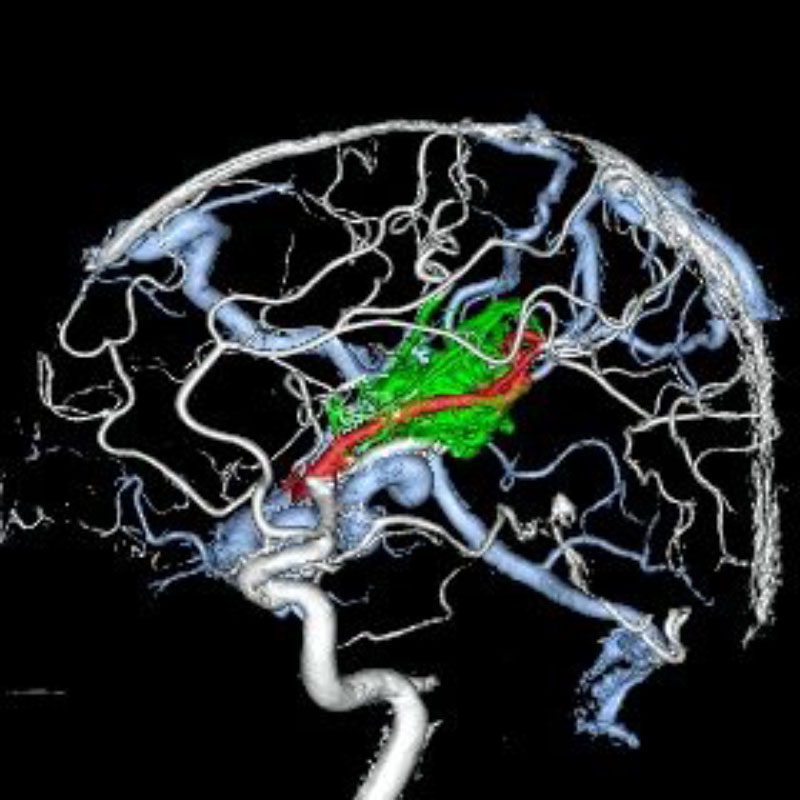

脳動静脈奇形

血管塞栓術

松田/濵田/元永